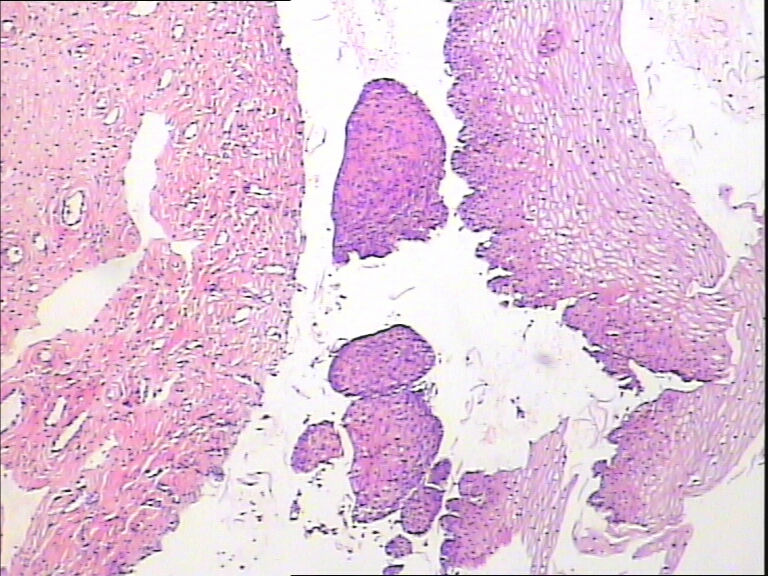

45y,触血,宫颈多点活检。